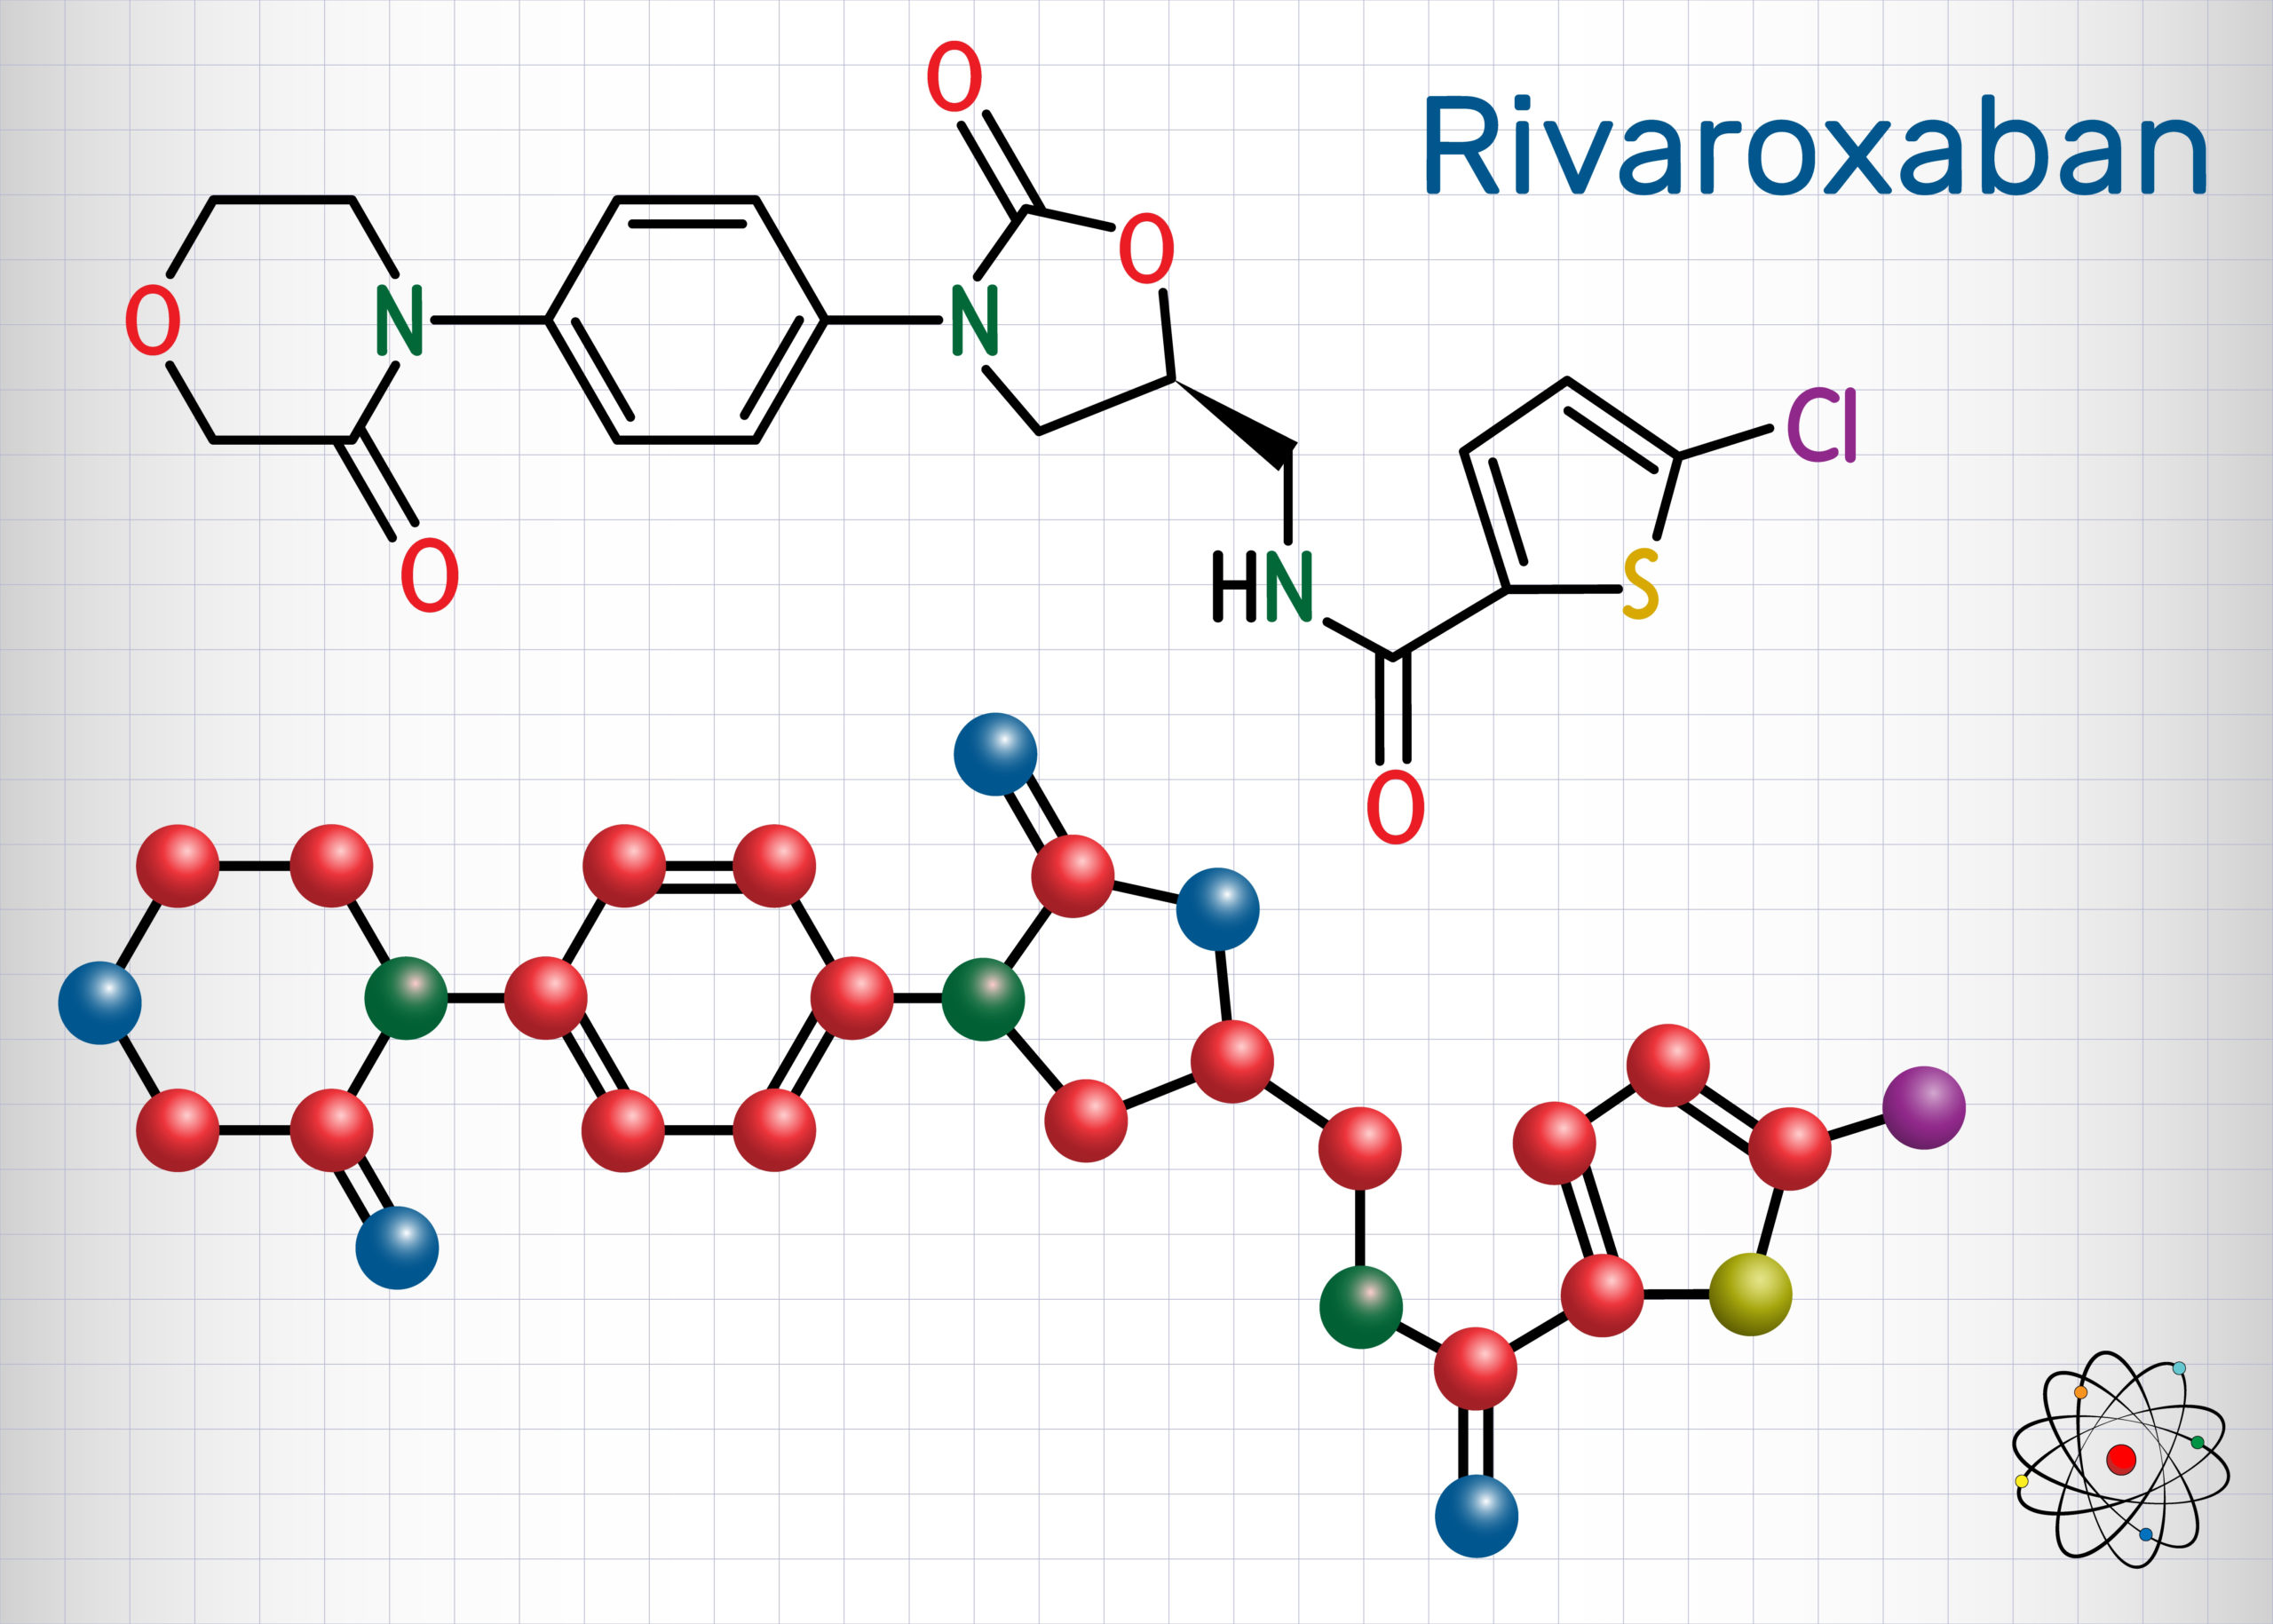

In patients with atrial fibrillation and coronary artery disease (CAD), researchers found that rivaroxaban monotherapy ...

Researchers in the Netherlands aimed to illuminate the clinical and economic effects of treatment with rivaroxaban from ...

Manesh R. Patel, MD, Professor of Medicine and Chief of Cardiology at Duke University School of Medicine, talks with ...